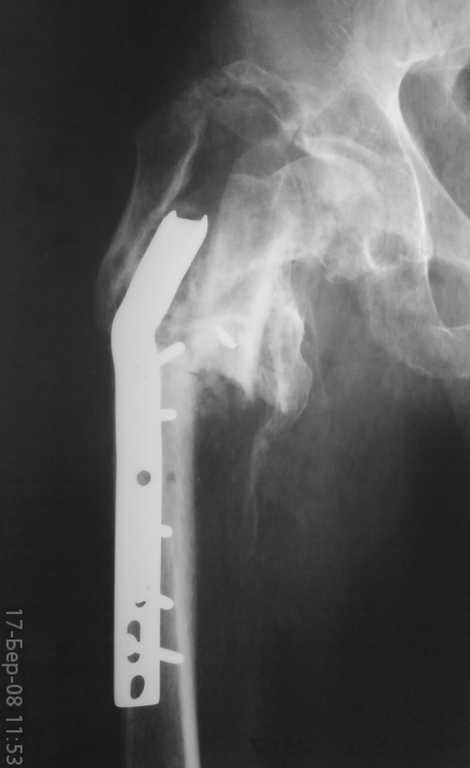

неправильно консолидированный перелом вертельной области

Ув.коллегиПоступил больной год назад прооперированный-МОС вертельной области.

Жалобы на невозможность ходьбы и сильное(15-18 см)укорочение ноги. Что делать? Заранее благодарен.Тарас Рокита ,Киевская ГБ 7

судя по снимкам укорочение должно быть около 7-8 см. Целесообразно выполнить читаемые снимки.

варианты лечения, на мой взгляд:

1 удаление пластины

2. остеотомия

3. низведение бедра в АВФ " таз- бедро"

4. первично ревизионое эндопротезирование.

К обсуждению 4 пункта будет целесообразно вернуться после выполнения первых трех.

Для начала определить величину и причину укорочения не по жалобам больного, а сделав соответствующие измерения и рентгеновские снимки,

КТ.

Как общий подход - удаление несостоятельного фиксатора, восстановление длины и оси сегмента (не обязательно все это делать в области

несращения), окончательная фиксация.

В данном случае надо еще разбираться, что за "оссификаты" над большим вертелом, что за отломок на фоне шейки, что с суставом - можно

ли рассчитывать на движения после коррекции, или уже думать о протезе.

Можно ли организовать снимок таза и боковой снимок? Что за имплант, если Blade Plate тогда сколько градусный? Что намерены делать?